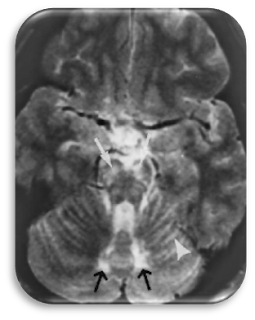

“A ressonância

magnética (RM) tornou-se essencial para avaliar quer o inicio do quadro clínico

quer a sua evolução. A RN permite assim detetar precocemente lesões no sistema

nervoso central e periférico” bem como distinguir os diferentes fenótipos

e com isso fazer o diagnóstico diferencial (Kim & Kim, 2005).

“Até

50% dos indivíduos do sexo masculino com AMN apresentam evidências radiológicas

da desmielinização cerebral na ressonância magnética (RM)” (Khandwala, et.

al., 2004). Podemos observar na RM:

1. Sem

achados cerebrais (55%) – AMN “Pura”: Atrofia da medula espinhal;

2. AMN

com envolvimento cerebral – Degeneração do Tratos Longos; Envolvimento

bilateral do trato corticoespinhal;